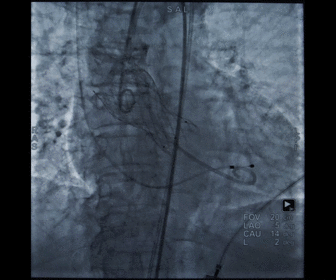

根部造影

球囊预扩

胶囊腔定位

瓣膜释放

造影观察瓣膜形态